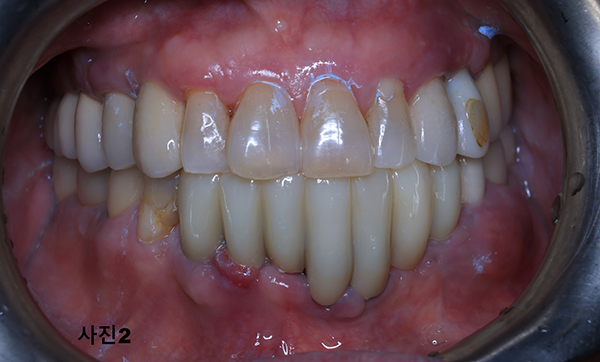

2025년 10월 아래턱이 심하게 붓고 너무나도 아픈 모습으로 내원하신 70대 여성분 (사진1)과

X-ray 촬영 (사진2)후에 구강검진을 하여보니 임플란트를 식립한 모든 부위에 심한 부종과 통증이 그리고 고름이 흘러나오고 있었다.